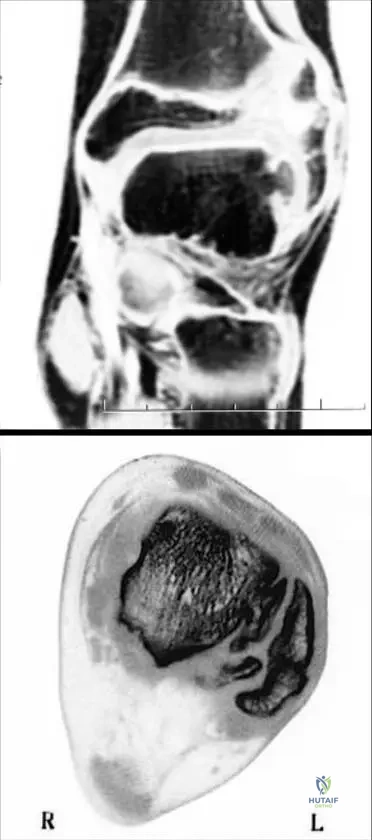

This module contains 50 advanced orthopedic multiple-choice questions meticulously developed to mirror the Arab Board of Orthopedic Surgery examinations. These questions are derived from the clinical teaching case: 1.5.1 Dysplasia Epiphysealis Hemimelica.